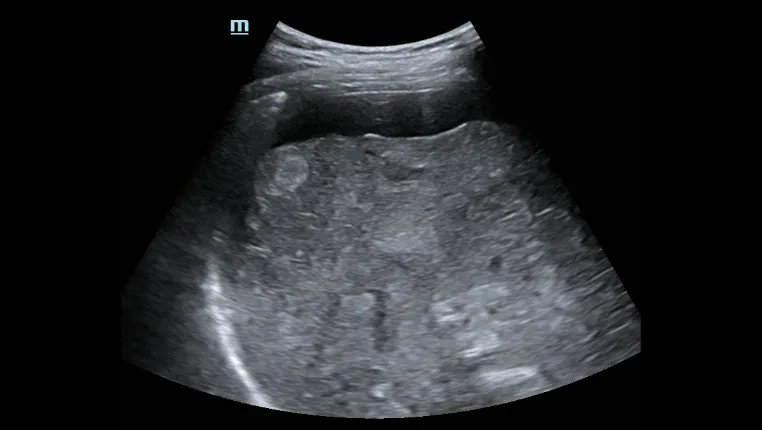

- Превосходное ультразвуковое изображение и функциональность позволяют всесторонне оценить морфологию и гемодинамику печени.

Асцит печени

Оценка морфологии печениЭргономичный дизайн